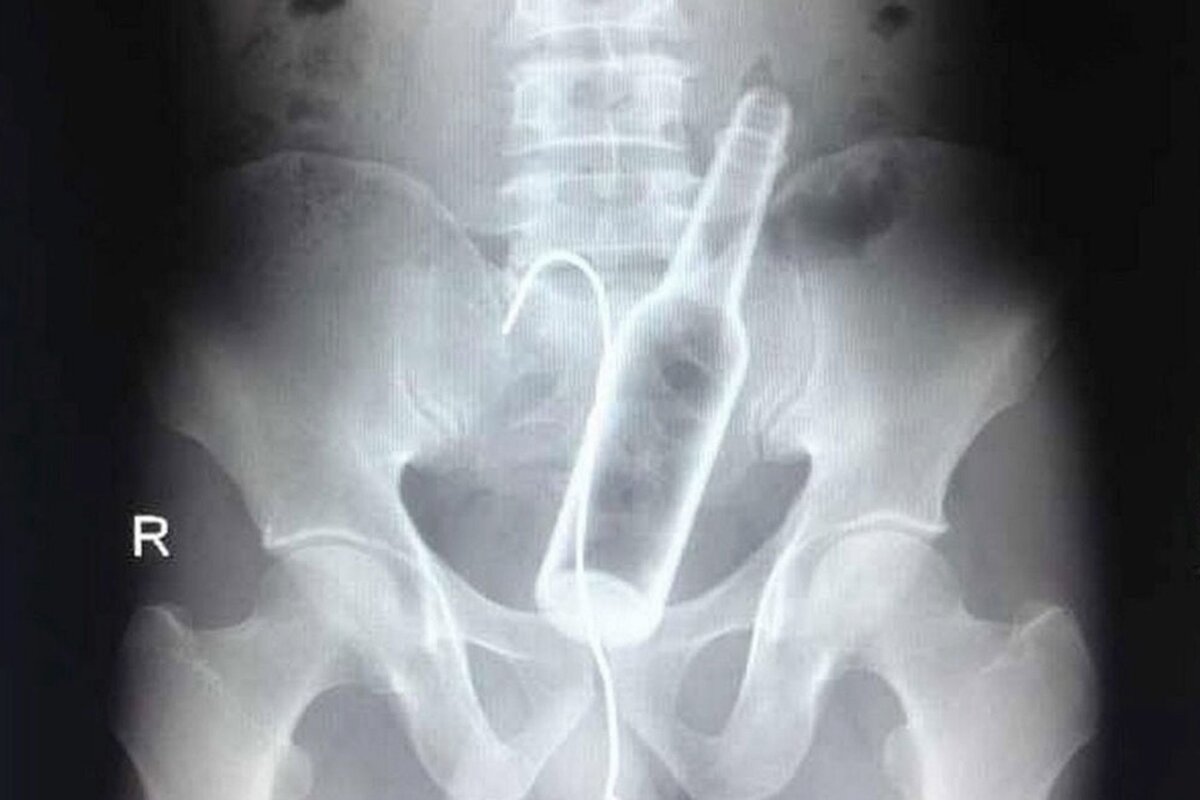

Ножницы

После еды 27-летний Конг Лин решил воспользоваться 10-сантиметровыми маникюрными ножницами в качестве зубочистки. Но, поскольку один из его друзей рассказывал анекдот, Конг рассмеялся и проглотил ножницы.